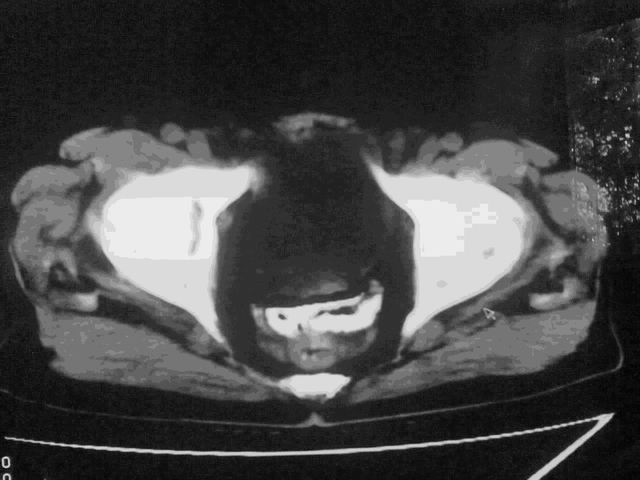

我这个考考大家眼力,看看是升结肠ca还是降结肠ca

下面的是4小时后的,